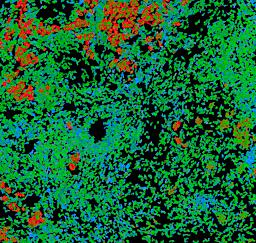

Pancreatic ductal adenocarcinoma is a lethal disease with limited treatment options and poor survival. We studied 83 spatial samples from 31 patients (11 treatment-naïve and 20 treated) using single-cell/nucleus RNA sequencing, bulk-proteogenomics, spatial transcriptomics and cellular imaging. Subpopulations of tumor cells exhibited signatures of proliferation, KRAS signaling, cell stress and epithelial-to-mesenchymal transition. Mapping mutations and copy number events distinguished tumor populations from normal and transitional cells, including acinar-to-ductal metaplasia and pancreatic intraepithelial neoplasia. Pathology-assisted deconvolution of spatial transcriptomic data identified tumor and transitional subpopulations with distinct histological features. We showed coordinated expression of TIGIT in exhausted and regulatory T cells and Nectin in tumor cells. Chemo-resistant samples contain a threefold enrichment of inflammatory cancer-associated fibroblasts that upregulate metallothioneins. Our study reveals a deeper understanding of the intricate substructure of pancreatic ductal adenocarcinoma tumors that could help improve therapy for patients with this disease.